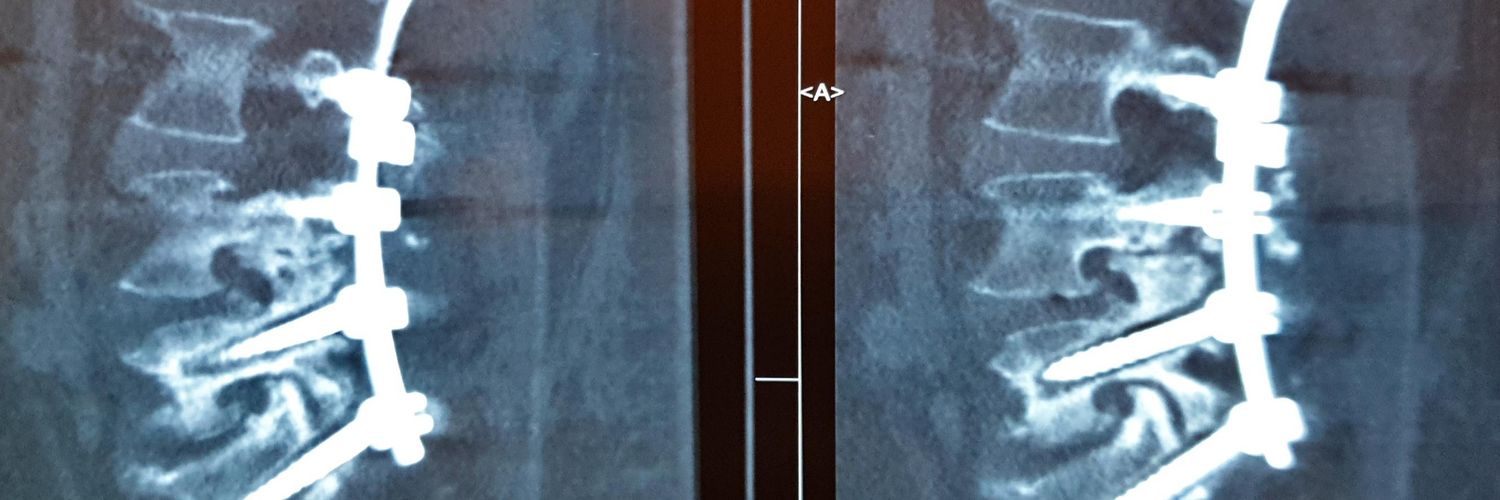

من یک پزشکم

سوگند خوردهام انسانها را درمان کنم و حافظ اسرارشون باشم

اگر نیاز به مشورت پزشکی داشتید، به من پیام بدید

🇮🇷 پزشک / بیماریهای ستونفقرات / عضو انجمن پی و مهره ایران / #بدون_سهمیه کارشناس ارشد جامعهشناسی - INFP-A - بنیانگذار #کافیگپ @CoffeeGap_ 🇮🇷